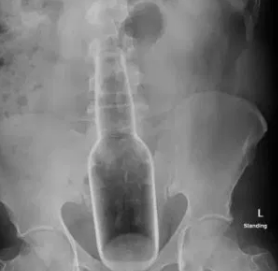

The doctor then found a hard substance in his rectum and instantly asked him to get an X-ray done.

He went for it and they found out a traditional mosquito replete liquid’s bottle inside of him. The bottle was 7 inches long and 2 inches wide.